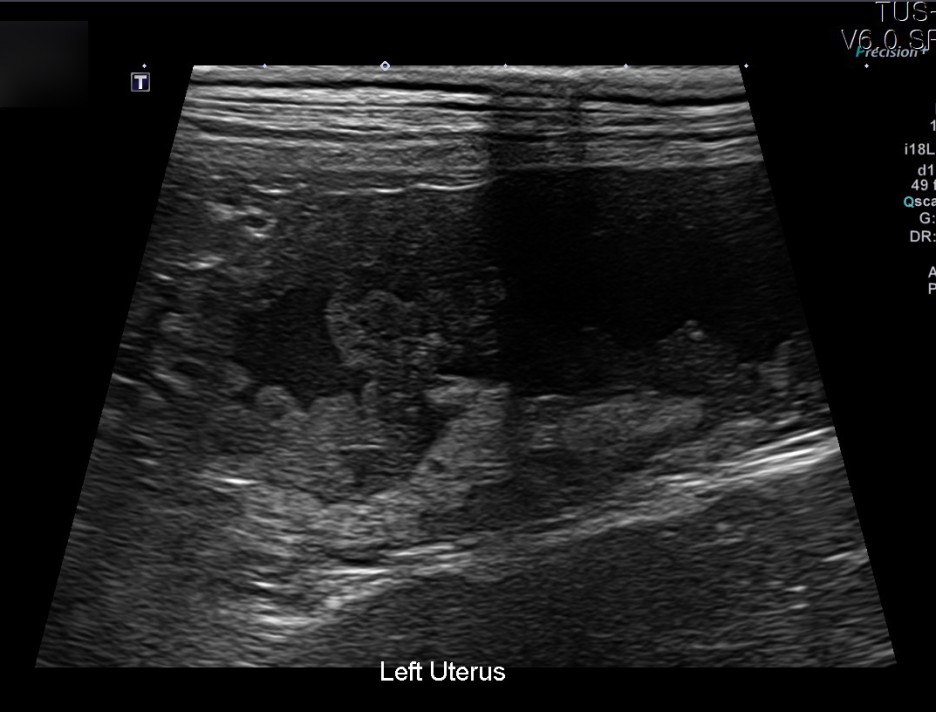

이어 진행된 초음파 검사에서는 자궁축농증으로 인해 내막이 두꺼워지고 크기가 커지는 염증성 변화가 진행되고 있었습니다.

✔US 양 자궁내막증식, 자궁각내삼출물에 의한 심한 확장소견